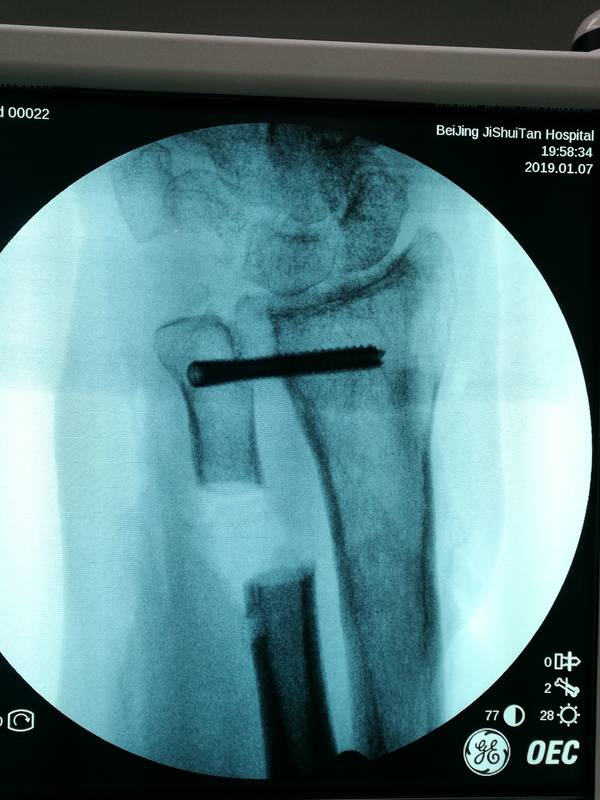

楼主| 发表于 2019-1-7 22:39:25 | 显示全部楼层

手功能重建,

尺骨远端截骨

s—k手术

IMG_20190107_184307.jpg

IMG_20190107_192748.jpg